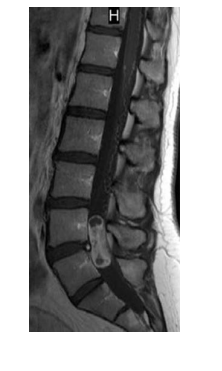

A 31-year-old man presents with back pain and erectile dysfunction. MRI is performed. Which one of the following statements regarding further management is key?

a. Gross total resection is the next appropriate step

b. Craniospinal axis MRI should be performed

c. External beam radiotherapy is critical after gross total resection

d. Etoposide chemotherapy is critical after subtotal resection

e. Conservative management with surveil- lance imaging is recommended

A

Myxopapillary ependymomas are most commonly benign and localize most often to the filum termi- nale and conus medullaris. They differ from other ependymomas morphologically and biologically and often resemble chordomas or chondrosarco- mas; immunohistochemical analysis is frequently required for differentiation. Myxopapillary epen- dymomas manifest in younger individuals, in com- parison with cellular ependymomas, and are also more common in male patients. They display large variations in size and are associated with scalloping of the vertebral body and enlargement of the neu- ral foramina. On T1-weighted imaging, myxopa- pillary ependymomas are most often isointense or hypointense; however, in some instances, they have displayed hyperintensity on T1-weighted imaging because of hemorrhage or their mucin content. On T2-weighted imaging, these tumors are most often hyperintense. Polar cysts are also common findings in myxopapillary ependymo- mas. Myxopapillary ependymomas are low-grade tumors that typically occur in the lumbosacral

region (filum terminale), are well-differentiated, and are often encapsulated but can seed the CSF, typically with “drop metastases” at the thecal sac. Myxopapillary ependymomas often progress slowly and cause milder-than-expected neuro- logic deficits for their size. These tumors repre- sent a special variant of ependymoma found almost exclusively in the region of the filum termi- nale, although occasionally they have been found higher in the spinal cord or, rarely, in the brain. They may occur at any age, but most arise in the fourth decade. Myxopapillary ependymomas characteristically form a sausage-shaped mass in the lumbosacral region, displacing spinal nerve roots of the cauda equina. Their biologic behavior is usually benign, but because of their location they are often associated with significant compression- induced paralysis. Treatment consists of local excision, which must often be only partial because of the tumor’s location; approximately 20% recur even after complete initial resection. Metastases infiltrating the CSF and extradural space may occur, but transformation to anaplastic variants is extremely rare. Myxopapillary subtypes appear to be associated with a favorable prognosis, poten- tially because of ease of resection because of their anatomic location. Patients who are able to achieve GTR have improved outcomes and the upfront addition of radiation therapy is of ques- tionable benefit. However, one study suggests that pediatric patients with this tumor had higher recurrence rates, even in the setting of GTR, and appeared to benefit from postoperative irradi- ation. A retrospective review from the Rare Can- cer Network suggests that higher postoperative radiation dose (>50.4 Gy) for the myxopapillary subtype may be associated with improved PFS.

A 31-year-old man presents with back pain and erectile dysfunction. MRI is performed. Which one of the following statements

regarding further management is key?

e. Conservative management with surveillance imaging is recommended

b. Craniospinal axis MRI should be

performed

Myxopapillary ependymomas are most commonly

benign and localize most often to the filum terminale and conus medullaris. They differ from other ependymomas morphologically and biologically and often resemble chordomas or chondrosarcomas; immunohistochemical analysis is frequently required for differentiation. Myxopapillary ependymomas manifest in younger individuals, in comparison with cellular ependymomas, and are also more common inmale patients. They display large variations in size and are associated with scalloping of the vertebral body and enlargement of the neural foramina. On T1-weighted imaging, myxopapillary ependymomas are most often isointense or hypointense; however, in some instances, they have displayed hyperintensity on T1-weighted imaging because of hemorrhage or their mucin content. On T2-weighted imaging, these tumors are most often hyperintense. Polar cysts are also common findings in myxopapillary ependymomas. Myxopapillary ependymomas are low-grade tumors that typically occur in the lumbosacral region (filum terminale), are well-differentiated, and are often encapsulated but can seed the CSF, typically with “drop metastases” at the thecal sac. Myxopapillary ependymomas often progressslowly and cause milder-than-expected neurologic deficits for their size. These tumors represent a special variant of ependymoma found

almost exclusively in the region of the filum terminale, although occasionally they have been found higher in the spinal cord or, rarely, in the brain.

They may occur at any age, but most arise in the

fourth decade. Myxopapillary ependymomas

characteristically form a sausage-shaped mass in

the lumbosacral region, displacing spinal nerve

roots of the cauda equina. Their biologic behavior

is usually benign, but because of their location they

are often associated with significant compressioninduced paralysis. Treatment consists of local excision, which must often be only partial because of the tumor’s location; approximately 20% recur even after complete initial resection. Metastases infiltrating the CSF and extradural space may occur, but transformation to anaplastic variants is extremely rare. Myxopapillary subtypes appear to be associated with a favorable prognosis, potentially because of ease of resection because of their anatomic location. Patients who are able to achieve GTR have improved outcomes and the upfront addition of radiation therapy is of questionable benefit. However, one study suggests that pediatric patients with this tumor had higher

recurrence rates, even in the setting of GTR,

and appeared to benefit from postoperative irradiation. A retrospective review from the Rare Cancer Network suggests that higher postoperative radiation dose (>50.4 Gy) for the myxopapillary subtype may be associated with improved PFS.